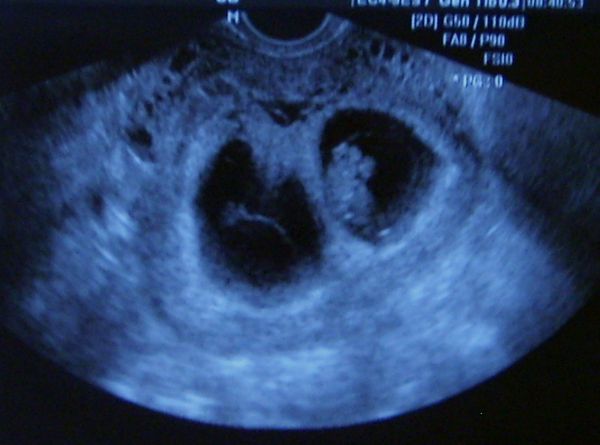

Figyu! Ha ugyanazon az oldalon van mindkét gyerek, akkor nem nyomják egymást? Nekem ez a legnagyobb parám, hogy nem lehet túl kényelmes odabenn nekik, csak nehogy ki akarjanak jönni idő előtt.